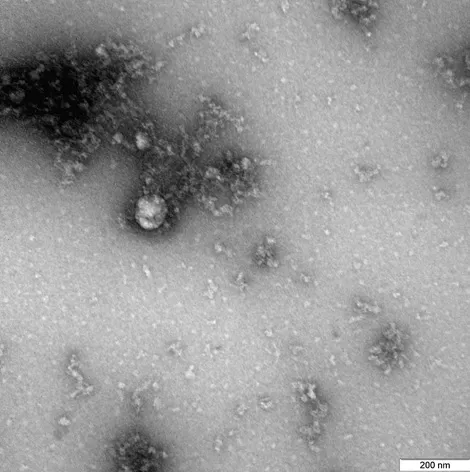

Изображение нового штамма коронавируса, выделенный от пациента в декабре 2020 года, первым в мире получил Новосибирский научный институт "Вектор".

Фотография получена при 100000-кратном увеличении с помощью трансмиссионного электронного микроскопа. На фото видна округлой формы вирусная частица диаметром около 140 нанометров. Также на фотографии изображены спикулы вируса, то есть выросты на его поверхности длиной около 20 нанометров.

Снимок сделан учеными в рамках изучения свойств данного варианта коронавируса. Специалисты с использованием лабораторных животных исследуют структурные особенности британского штамма, а также его проявления в клеточных культурах и экспериментальных моделях.

Фото rospotrebnadzor.ru